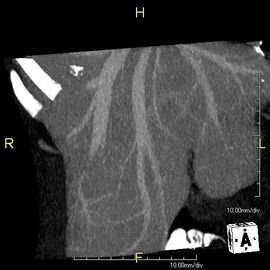

With the recent advances of noninvasive imaging, living liver donors usually have to undergo imaging examinations for liver anatomy to decide if the anatomy is feasible for donation. The evaluation is usually performed by multidetector row computed tomography (MDCT) and magnetic resonance imaging (MRI). MDCT is good in vascular anatomy and volumetry. MRI is used for biliary tree anatomy. Donors with very unusual vascular anatomy, which makes them unsuitable for donation, could be screened out to avoid unnecessary operations.